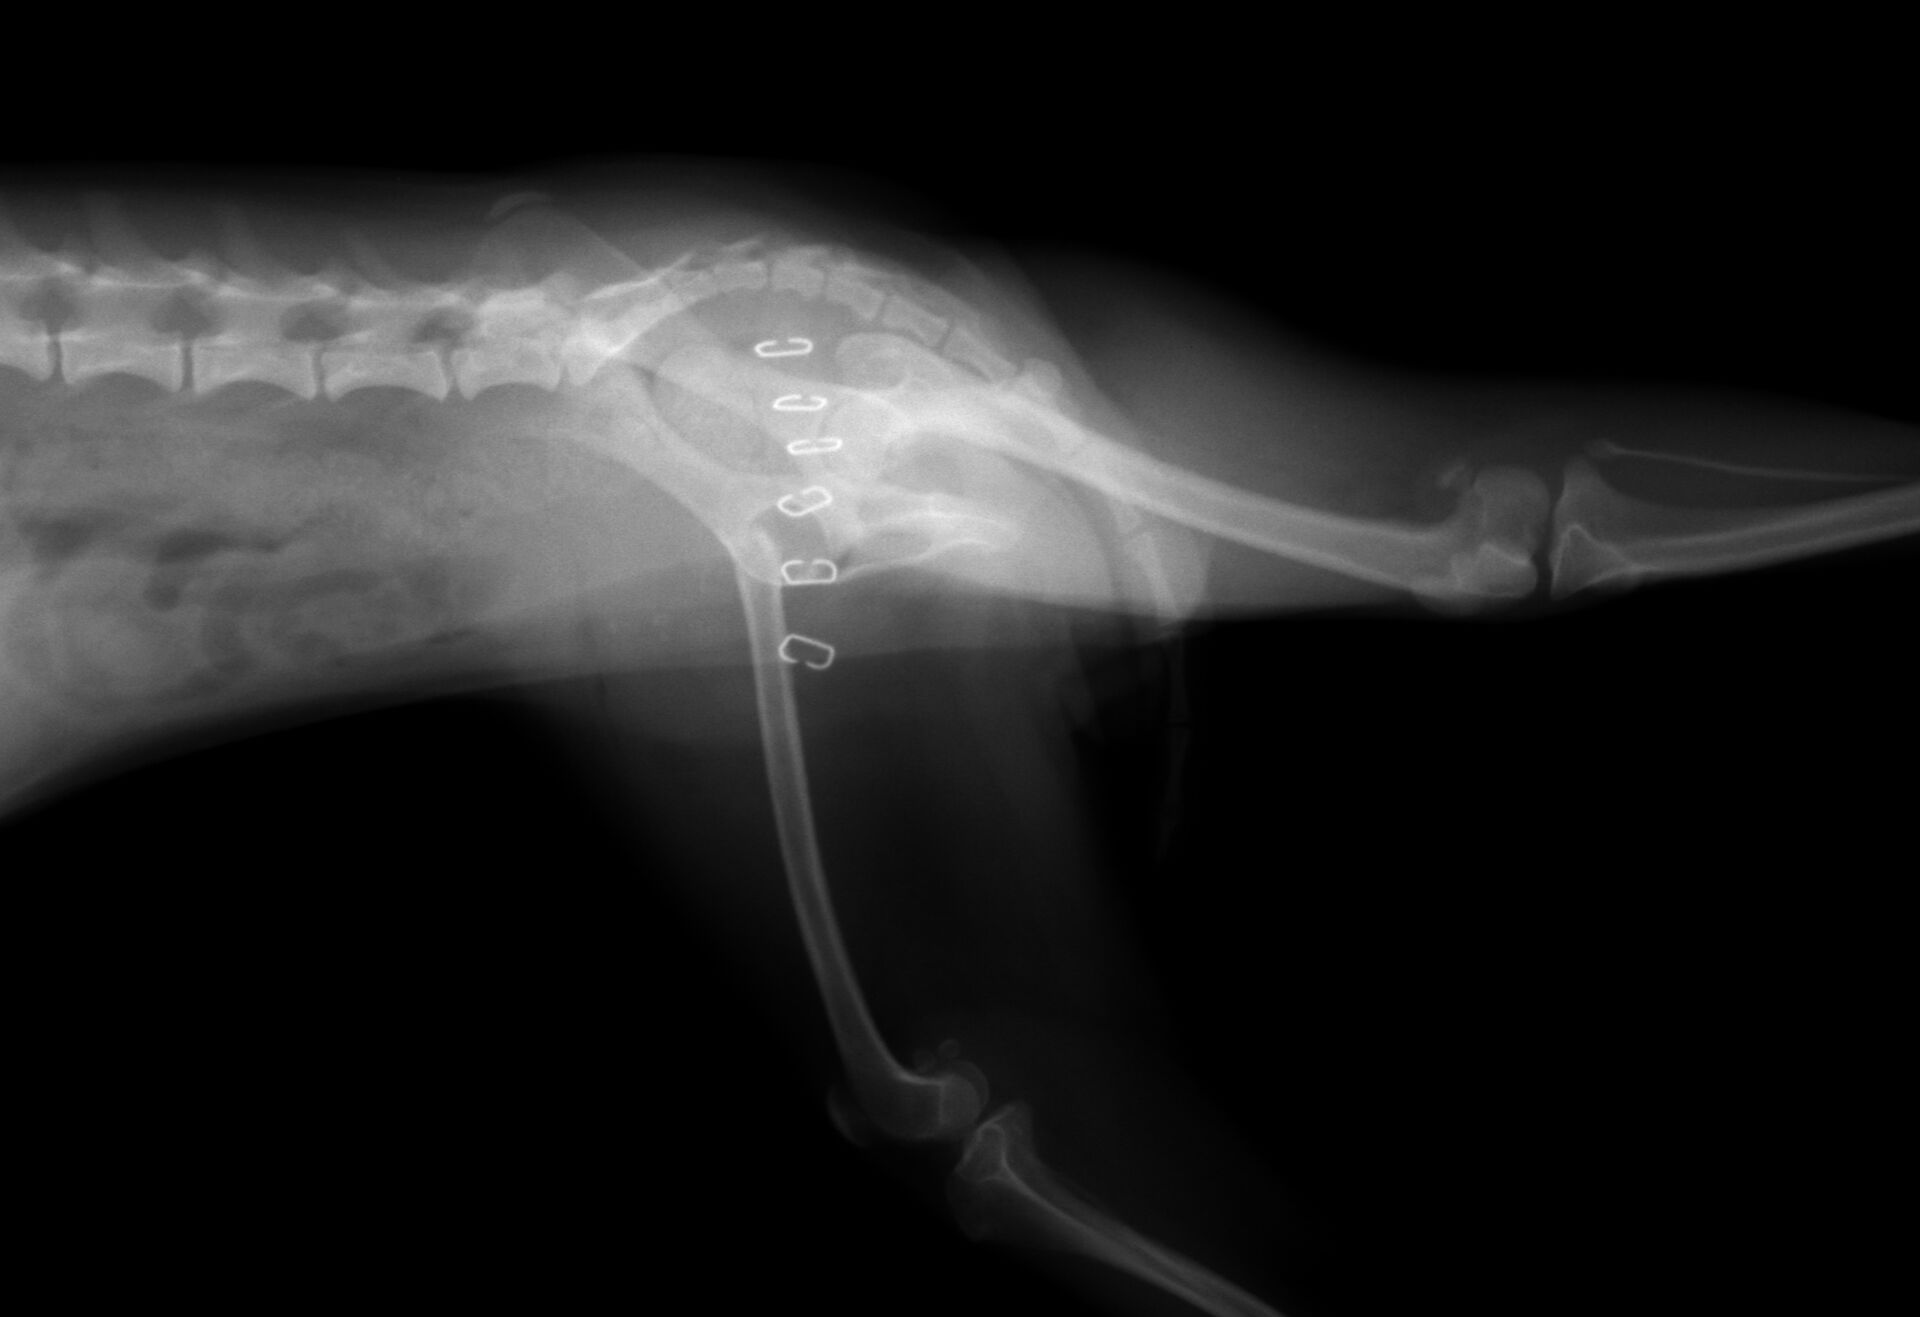

実際の手術後の写真が下の写真です。

右脚の大腿骨頭が無くなっているのがわかります。